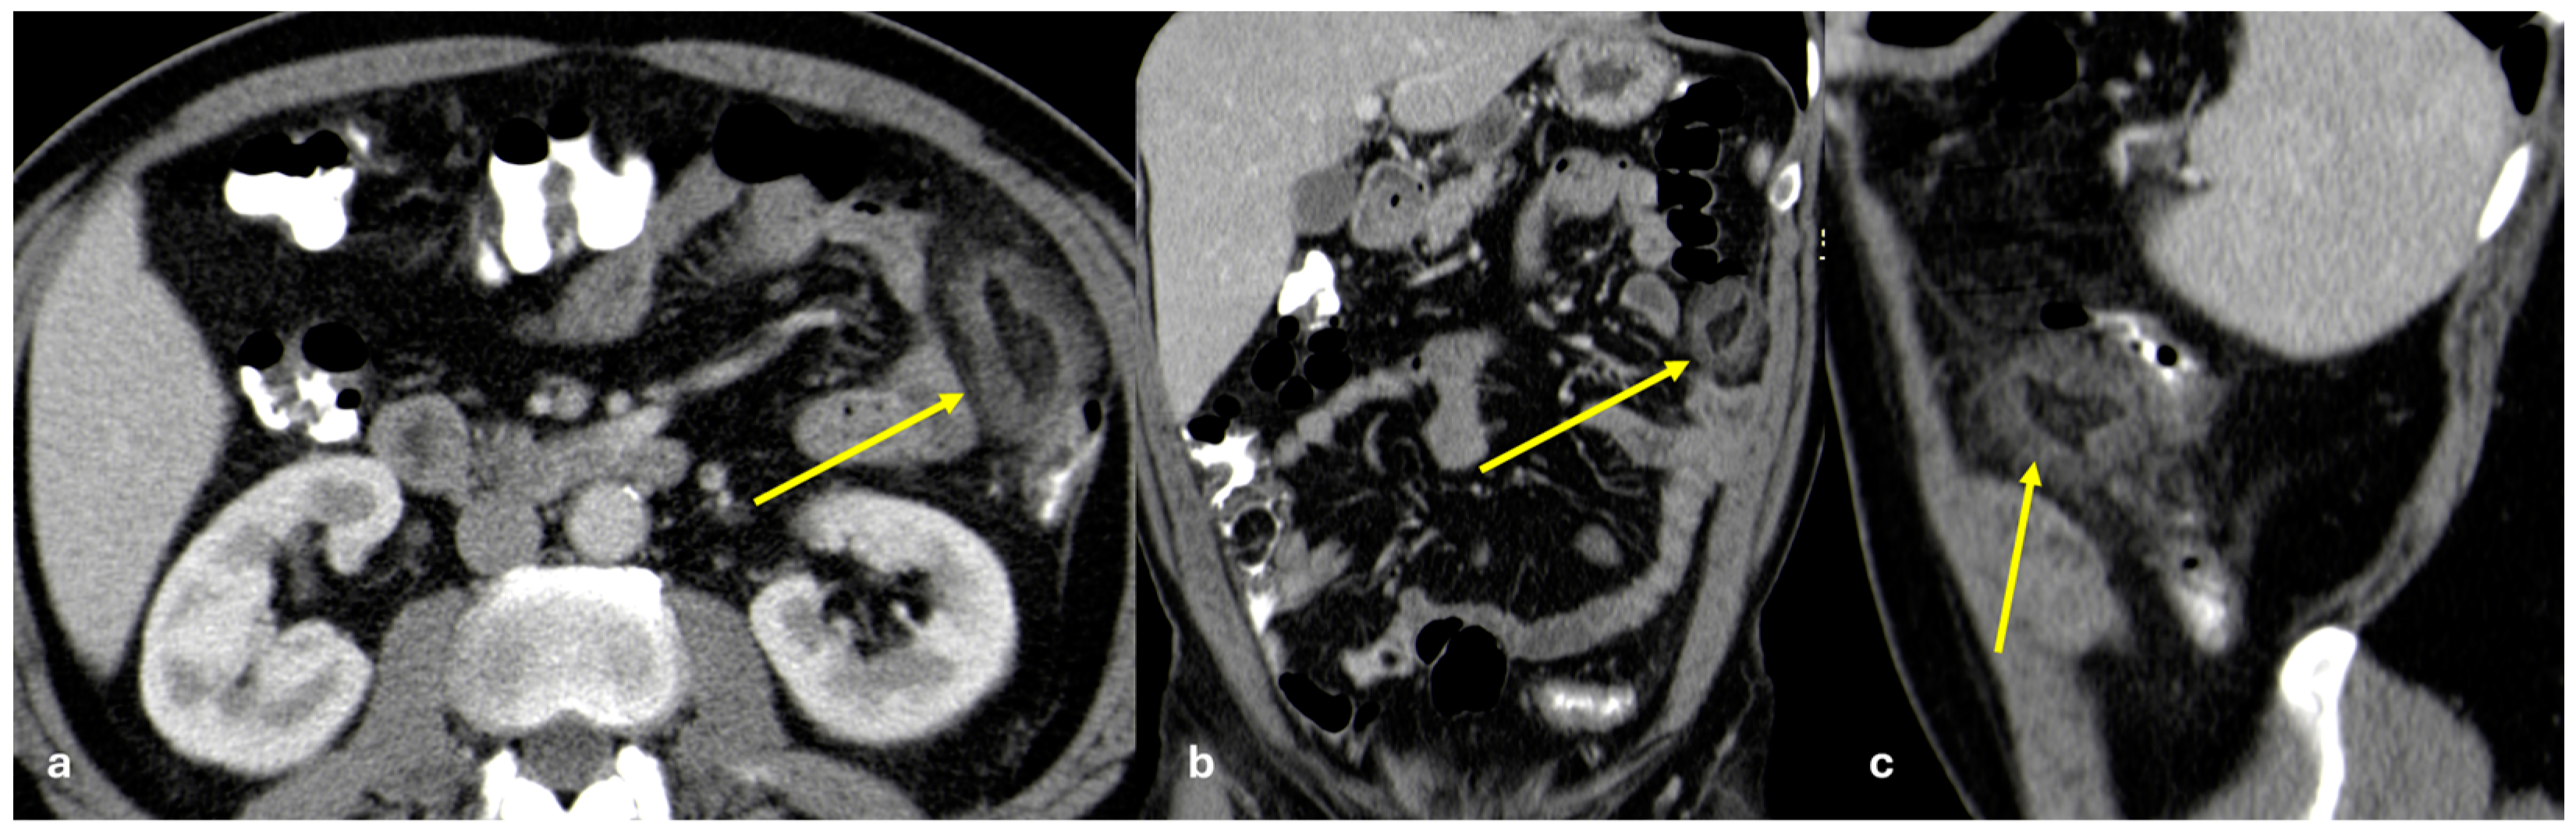

- Micro-nodular pattern: micro-nodules with a diameter ≤ 5 mm (Figure 1);

- Nodular pattern: nodules with a diameter > 5 mm (Figure 2a);

- “Omental cake”: nodular thickening of the omentum (Figure 2b);

- Plaque pattern: confluent nodular plaques, typically involving the lower surface of the right diaphragm (Figure 3);